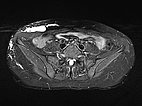

Coronal, T2-weighted, fat-suppressed MRI of the lower abdomen at the level of the groin. Normal inguinal lymph nodes. The lymphatic malformation of the abdominal wall presents as large, dysplastic, balloon-like, septated cysts that are grossly hyperintense (white).

Same slice in non-enhanced T1-weighted MRI. The cysts of the lymphatic malformation are isointense to the surrounding musculature. Thus, the cysts do not contain blood or high protein content.

Transverse, T2-weighted, fat-suppressed MRI at the level of the iliac crest shows additional extension of the lymphatic malformation to the right flank. Only the epifascial portions of the abdominal wall and trunk wall are involved.

Transverse T1-weighted, fat-suppressed MRI after contrast administration shows only minimal enhancement of the thin walls of the lymphatic malformation. This is typical of a lymphatic malformation, as the liquid in the cysts (lymph) does not enhance.